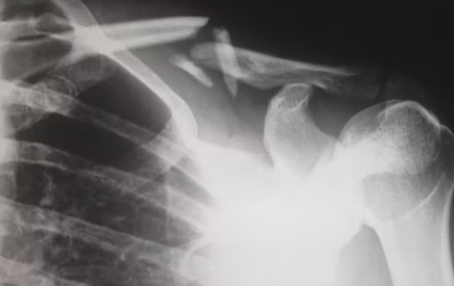

우선 용어가 어려워서 이 질환에 대해서 잘 모르시는 분들이 많은데요. 회전근개는 어깨 관절을 구성하는 4개의 어깨 근육, 즉 견갑하근, 극상근, 극하근, 소원근이 합해져 하나로 된 힘줄로 어깨가 360도 돌아가게 만들어주고 안정성을 유지하는 역할을 합니다.

어깨는 자유롭게 회전이 가능한 만큼 부상의 위험도 많은데요. 회전근개가 움직임에 의해서 충격을 받거나 노화 등 여러 가지 원인으로 인해 파열이 되어 기능장애, 염증 그리고 통증 등을 유발하게 되는 것이 어깨 회전근개파열입니다. 노년층에서 주로 발생을 하는데, 노화가 본격적으로 시작되는 30대에서 40대 사이에서도 많이 발생하고 있는 질환입니다.

다음 어깨 회전근개파열 증상으로는 관절염과 탈구입니다. 상완골두 즉 상완을 구성하는 뼈가 올라가 견봉과 맞닿으면서 뼈끼리 닿아서 관절염이 될 수 있습니다. 최악의 경우 파열이 왔는데 방치하면 탈구로 이어질 수 있으니 조심해야겠습니다.